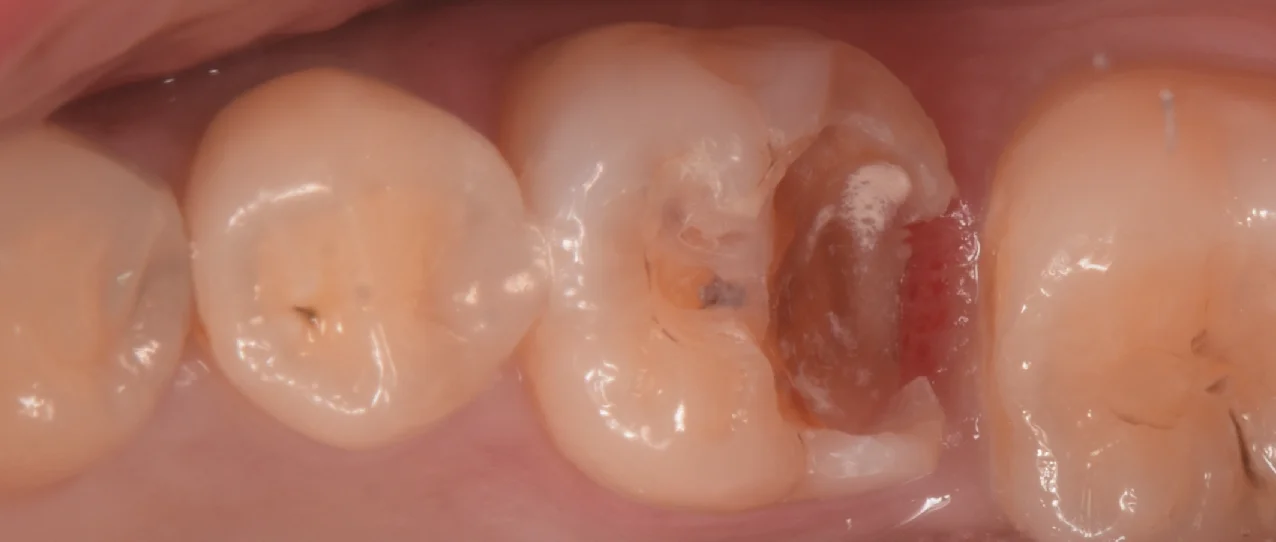

まずは術前からです。

2〜3年ほど前に入れたCAD/CAMインレーと呼ばれるものが入っています。

ここの一部が欠けてしまい、虫歯になっているようです。

2022年に保険適用となった治療法ですが・・・正直いって・・・予後は非常に悪いです。

さて、古い詰め物を除去したのがこちらになります。

接着が不十分のため、非常に広範囲に虫歯になってしまっています。

ただこれが術直後から接着が不十分だったのか、上記の通り接着が難しい材料のため、経年により接着が失われたのかはこの場ではわかりません。

ただこの方のこの歯に関しては2〜3年で接着面からダメになったという事実だけがあるという感じですね。